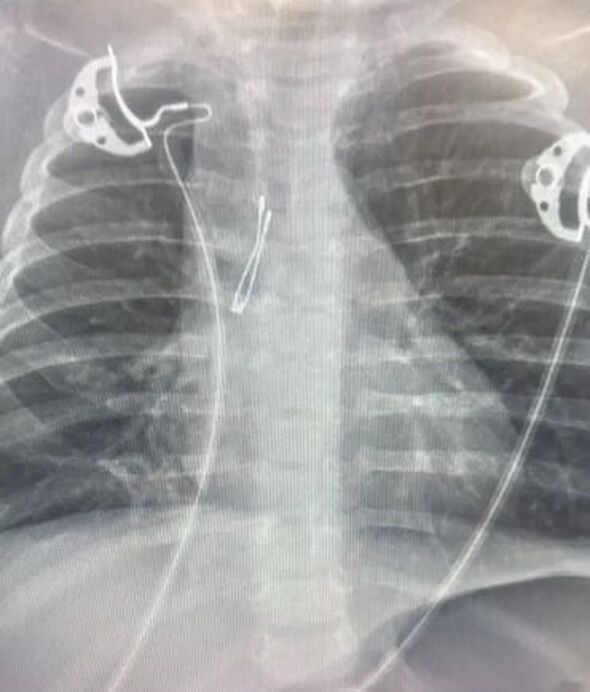

תינוקת בת שמונה חודשים הובהלה למרכז הרפואי וולפסון בחולון כשהיא סובלת ממצוקה נשימתית קשה. מה שהחל כשיעול תמים, התפתח במהירות למצב חירום רפואי של ממש כאשר הצוות הרפואי בבית החולים זיהה מיד את הסכנה: גוף זר שחוסם את דרכי האוויר של הפעוטה.

התינוקת הוכנסה בדחיפות לחדר הניתוח, שם תחת לחץ זמן פעל צוות רפואי משולב שכלל רופאי ריאות ילדים ורופאי אף, אוזן וגרון. לאחר שהתברר כי שיטת החילוץ הראשונה אינה מספיקה, עברו הרופאים במהירות לביצוע ברונכוסקופיה קשיחה. באמצעות פעולה מורכבת זו, שדרשה מיומנות ודיוק קריטי, הצליחו הרופאים לשלוף בבטחה נורת לד קטנה מריאתה של התינוקת. ההערכה היא כי מדובר בחלק מצעצוע שנפל על הרצפה ונבלע.

במרכז הרפואי וולפסון ציינו כי בזכות העבודה המסורה והמקצועית של הצוות המיומן, התינוקת שוחררה אתמול לביתה כשהיא במצב טוב ונושמת לרווחה.

הרופאים מזהירים ומדגישים בפני ההורים: במקרה של שיעול פתאומי, קושי בנשימה או שינוי בהתנהגות אצל פעוטות - אין להמתין. יש לפנות באופן מיידי לקבלת בדיקה וטיפול רפואי.